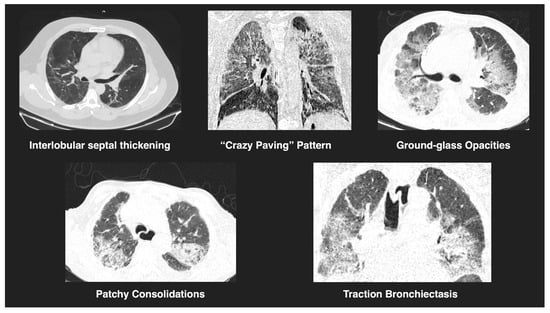

All chest CT scans were assessed for characteristic imaging features (Figure 1), including consolidation, ground-glass opacities, nodular lesions, lymphadenopathy, vascular thickening, and evidence of embolism (Figure 2). To quantify lung involvement, we used a semi-quantitative pulmonary damage severity index based on estimated parenchymal involvement in each of the five lung lobes. Each lobe was scored from 0 (no involvement) to 5 (more than 75% involvement), yielding a total score ranging from 0 to 25 per patient. This approach, previously validated in similar contexts [,], was selected over standardized diagnostic scoring systems such as CO-RADS or RALE due to its flexibility and broader applicability in comparative viral pneumonia analysis. Lymphadenopathy was defined as lymph nodes with a short-axis diameter greater than 1 cm. Vascular thickening was identified by abnormal vessel enlargement—either greater than nearby vessels in unaffected areas, larger than corresponding vessels in the contralateral lung, or demonstrating a lack of tapering toward the periphery.

Figure 1.

Representative tomographic features of viral pneumonia. CT images show key findings observed in COVID-19 and H1N1 cases, including interlobular septal thickening, a “crazy paving” pattern, ground-glass opacities, patchy consolidations, and traction bronchiectasis. These features reflect varying degrees of pulmonary involvement and are consistent with viral pneumonitis.